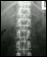

Now a month later, Dr. Smith said Tayler is healing very well. From the outside her incision looks good, but the before and after x-rays really show the change.

In spinal fusion for scoliosis, rods, hooks, wires, or screws are attached to the curved part of the backbone and the spine is straightened. Small pieces of bone are then put over the spine. The bone pieces will grow together with the spinal bone, fusing it into the proper position. Spinal fusion is major surgery that usually takes several hours to complete.

This year, just four years after her diagnosis, Tayler underwent spinal fusion, a special surgery to correct the curving of her spine. It's a procedure that used to take between eight and 12 hours and recovery would take months.